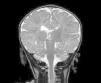

Se realizan las siguientes pruebas complementarias: radiografía de tórax donde se observa discreta cardiomegalia y signos de edema agudo de pulmón; ecografía abdominal (fig. 1) objetivándose un gran trombo que ocupa prácticamente toda la luz de la aorta abdominal desde la parte distal de la mesentérica superior hasta la bifurcación de ambas ilíacas. Ecografía transfontanelar: presencia de un trombo en el seno longitudinal superior, confirmado en la resonancia magnética (fig. 2) y en la angiografía cerebral (fig. 3) realizadas posteriormente.

Figura 2. Resonancia magnética donde se observa un trombo en el seno longitudinal superior.